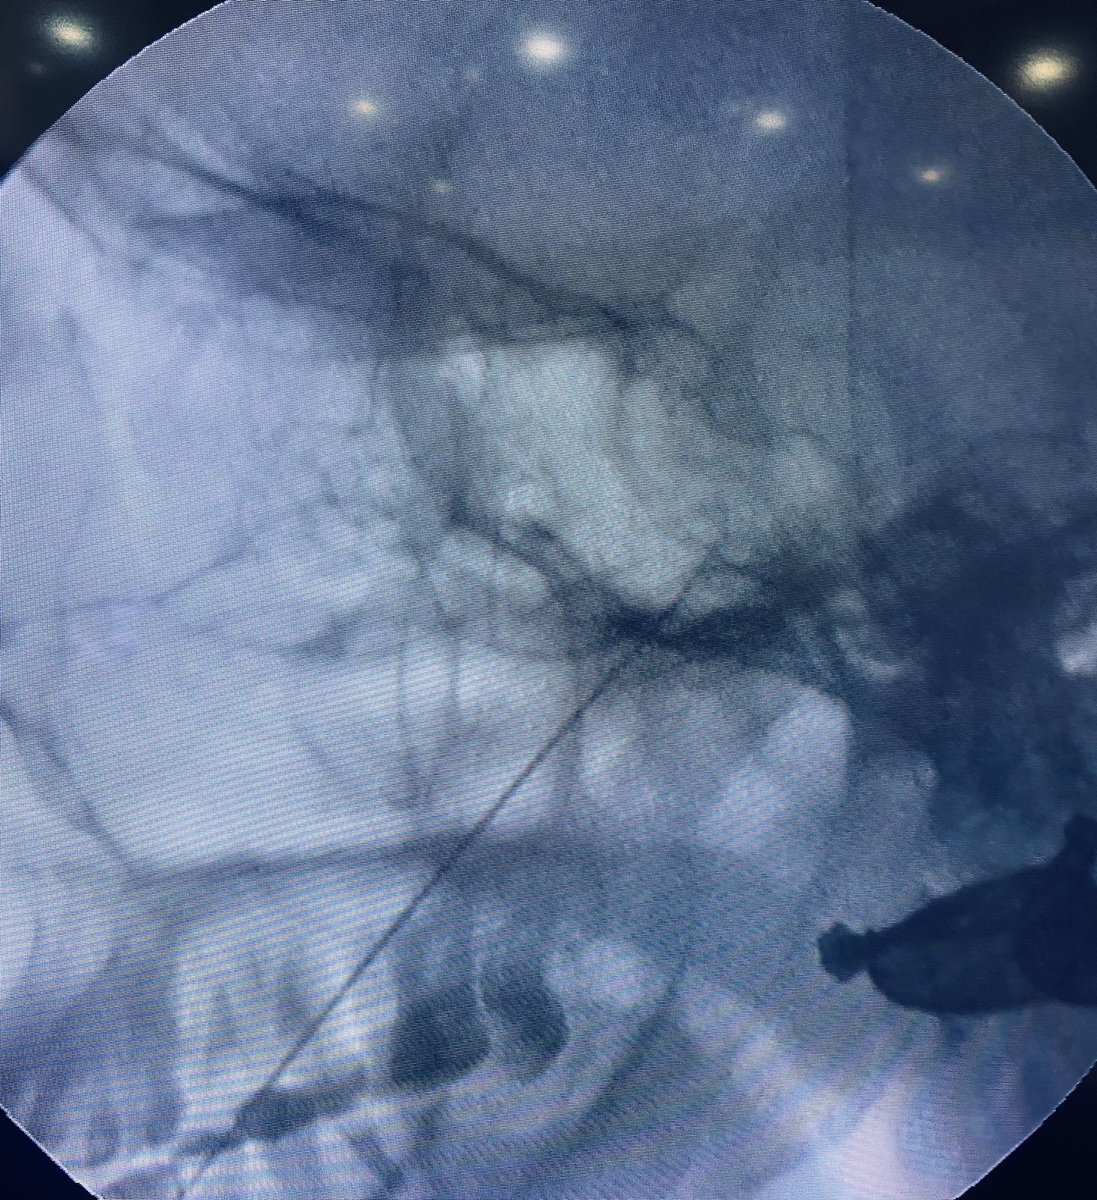

Severe facial pain after Failed MVD (micro vascular decompression) surgery for #Trigeminalneuralgia. Did RFA for this patient today. Difficult case as CSF was everywhere due to distorted anatomy. Selective mandibular/maxillary division ablated near the foramen. #Trigeminal

tariqtramboo's tweet image. Severe facial pain after Failed MVD (micro vascular decompression) surgery for #Trigeminalneuralgia. Did RFA for this patient today. Difficult case as CSF was everywhere due to distorted anatomy. Selective mandibular/maxillary division ablated near the foramen.  #Trigeminal

Radiofrequency procedure for #Trigeminal Neuralgia done just now at #Reliefpainservice kashmir. No sedation given. Pulsed RFA for 300 sec, before conventional RFA desensitises the ganglion for heated ablation (RFA). Patient did not require any sedation during the procedure.

tariqtramboo's tweet image. Radiofrequency procedure for #Trigeminal Neuralgia done just now at #Reliefpainservice kashmir.

No sedation given. Pulsed RFA for 300 sec, before conventional RFA desensitises the ganglion for heated ablation (RFA). Patient did not require any sedation during the procedure.